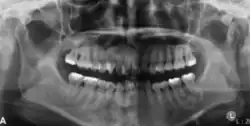

Radiographically, COF appears as a well-defined unilocular lesion. In large mandibular cases, it may cause downward bowing of the inferior border.[13] Tooth displacement is common, while root resorption is less frequently observed.[13] If untreated, the lesion can grow substantially. Surgically, COF is usually well-demarcated from the surrounding bone and often easily enucleated. Some lesions may also exhibit a distinct capsule.[11]

In its early stages, central ossifying fibroma (COF) appears as a small, well-defined radiolucent lesion due to its fibrous tissue content. Differential diagnoses at this stage include periapical pathology, central giant cell granuloma, and ameloblastoma.[22][23] As the lesion matures, it exhibits a mixed radiolucent-radiopaque appearance due to progressive calcification.[22] At this stage, it should be differentiated from other mixed jaw lesions such as fibrous dysplasia, calcifying epithelial odontogenic tumour, adenomatoid odontogenic tumour, and condensing osteitis.[22] In its mature form, COF may appear predominantly radiopaque, resembling lesions like odontomas, osteoblastomas, or osteosarcomas radiographically.

COF typically presents with well-defined, smooth, and often corticated borders. As a central lesion, it originates within the medullary bone and expands concentrically in all directions.[24] With growth, it may cause tooth displacement, root resorption, inferior displacement of the mandibular canal, and loss or alteration of the lamina dura of adjacent teeth.[25]

In conclusion, COF most commonly occurs in the mandible and expands from a central epicenter. Radiographically, it presents as a well-defined mixed-density lesion,[26] and Cone Beam CT (CBCT) plays a crucial role in its accurate diagnosis and assessment.

Central Ossifying Fibroma (COF) typically presents as a painless swelling in the posterior mandible, though maxillary involvement can also occur.[31] Larger lesions may lead to facial asymmetry and displacement of adjacent teeth.[32] Radiographically, COF appears as a well-circumscribed, mixed radiolucent–radiopaque lesion with a characteristic sclerotic border, and the degree of radiopacity reflects the stage of mineralization.[33] Cone-beam computed tomography (CBCT) offers detailed evaluation of cortical expansion, root displacement, and internal architecture.[34]